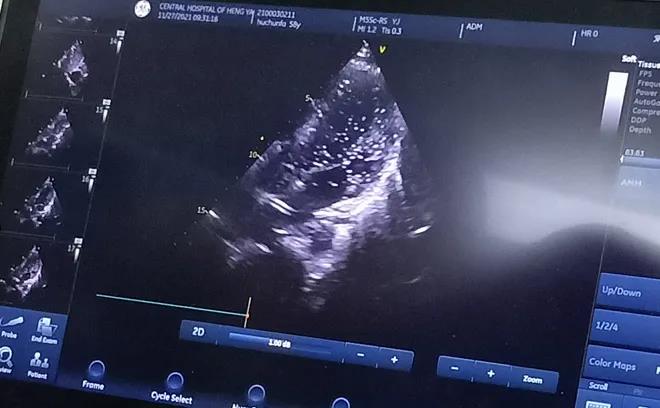

經(jīng)充分的術(shù)前準(zhǔn)備后, 11月27日上午,胡先生接受局部麻醉下經(jīng)皮介入PFO封堵術(shù),手術(shù)全程病人清醒,醫(yī)生一邊與胡先生交流,一邊進行手術(shù),術(shù)后無傷口創(chuàng)面。患者當(dāng)天即下床活動,復(fù)查心臟彩超提示封堵器位置良好。

胸超聲心動圖引導(dǎo)下經(jīng)股靜脈房間隔缺損封堵術(shù)是在胸超聲心動圖實時監(jiān)測下的封堵術(shù),與傳統(tǒng)開胸行房間隔缺損修補術(shù)相比,只需要通過大腿股靜脈進行穿刺便可完成,出血少、不縫針,真正做到了“微創(chuàng)”,創(chuàng)傷小且不影響美觀;與內(nèi)科介入下手術(shù)相比,又避免了X線對患者的放射損傷。在胸超聲實時引導(dǎo)下操作,定位準(zhǔn)確,隨時可調(diào)整封堵傘位置,適合于繼發(fā)孔房間隔缺損、室間隔缺損、動脈導(dǎo)管未閉等各種常見先天性心臟病的治療,對先心病心臟病患者的治療又提供了一項新的微創(chuàng)治療方法。該技術(shù)因創(chuàng)傷小、恢復(fù)快,術(shù)后3至5天即可出院。